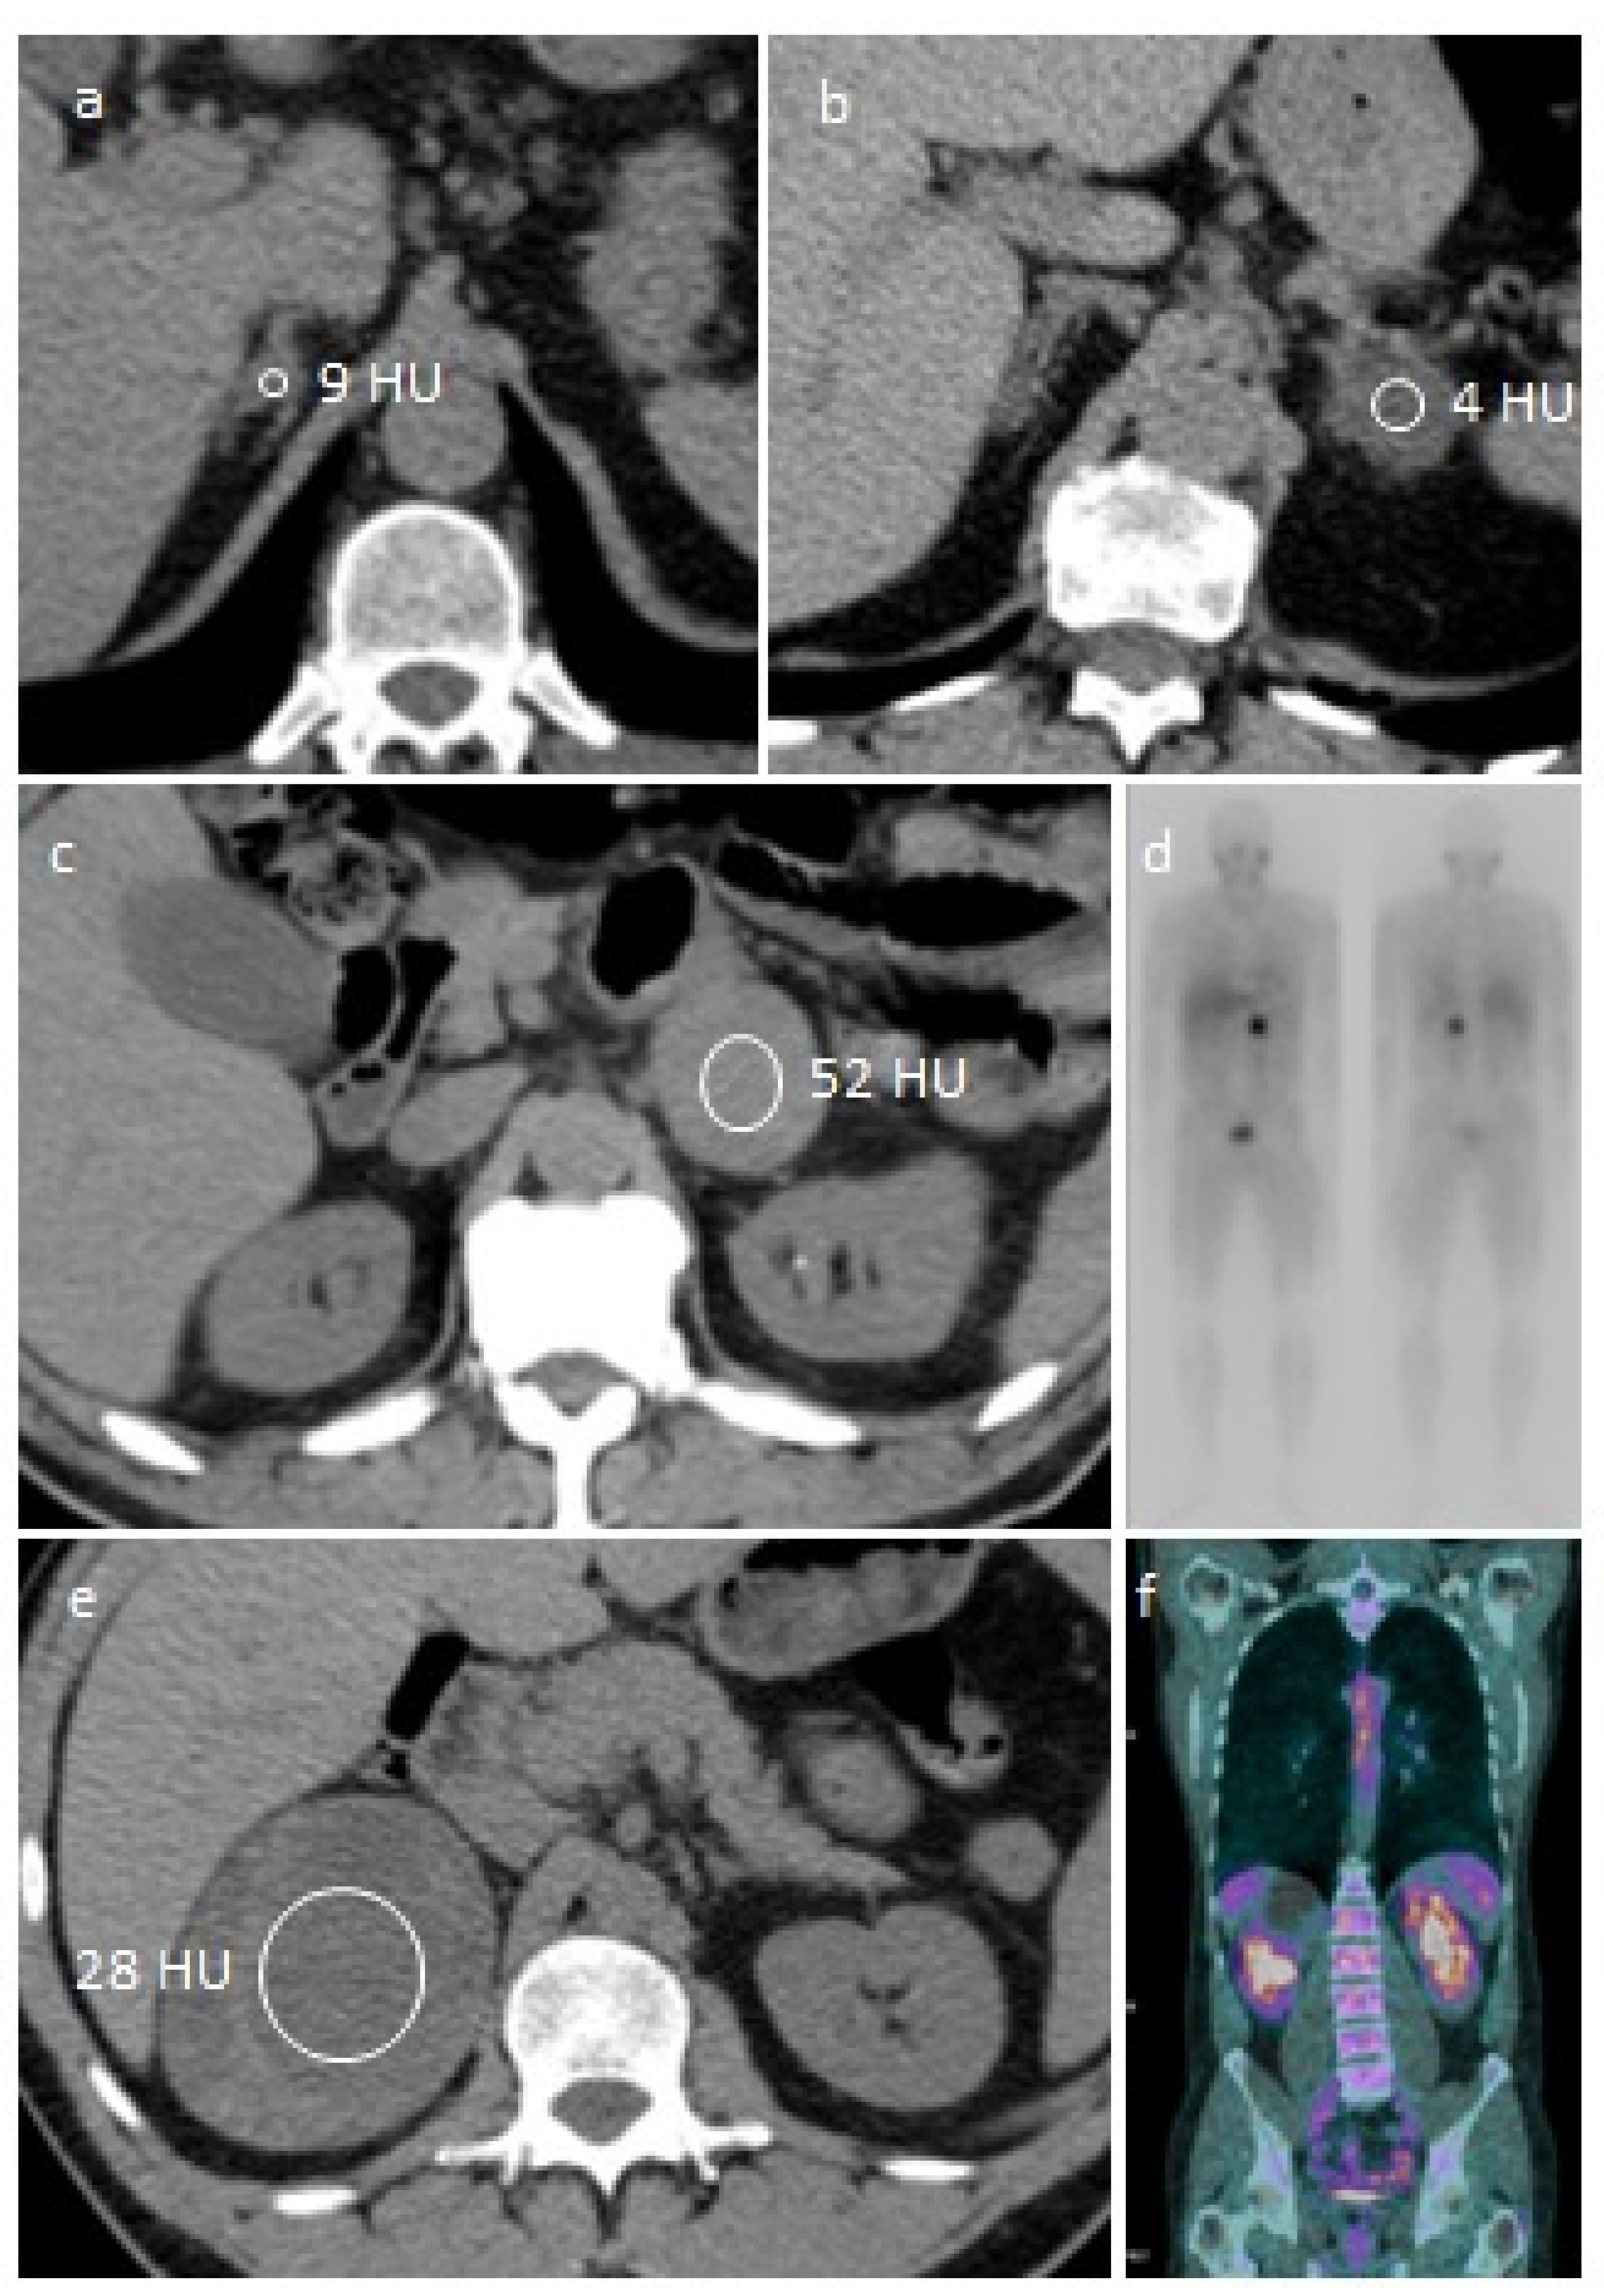

5. Potentially Malignant Adrenal Mass

5.1. Case 4

5.2. Perioperative Management of a Potentially Malignant Adrenal Mass